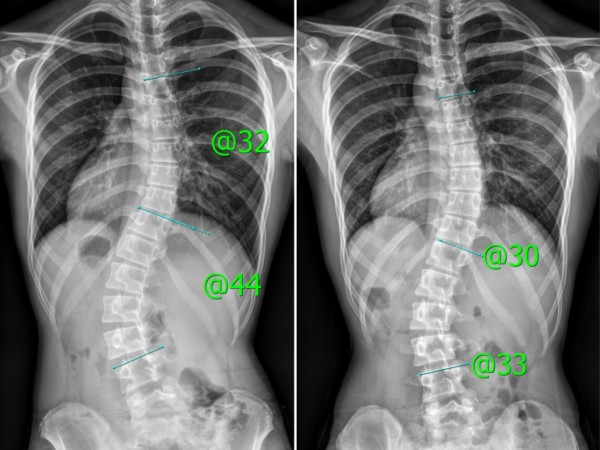

교정사례

PHS효과?